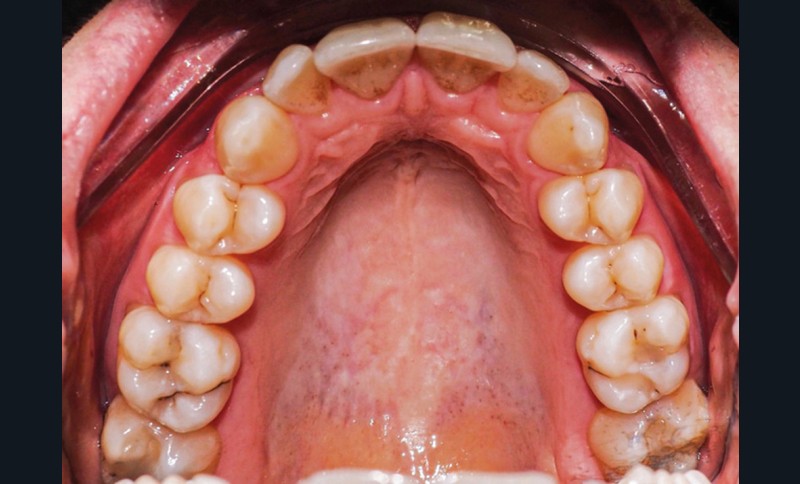

Examen endo-buccal (fig. 2a-e)

L’arcade maxillaire est parabolique, la 12 présente une légère mésio-rotation. L’arcade mandibulaire est également parabolique avec un encombrement antérieur estimé à 6 mm. On note une dyschromie de la 31, dont le test de vitalité est négatif. Le parodonte est fin.

En occlusion, on note une relation de Classe I molaire bilatérale avec un surplomb normal et une supraclusion. Les médianes incisives sont concordantes.

Les incisives maxillaires sont de forme triangulaire [1] et l’indice de Bolton est de 97 % qui traduit la présence d’une DDD par excès mandibulaire.